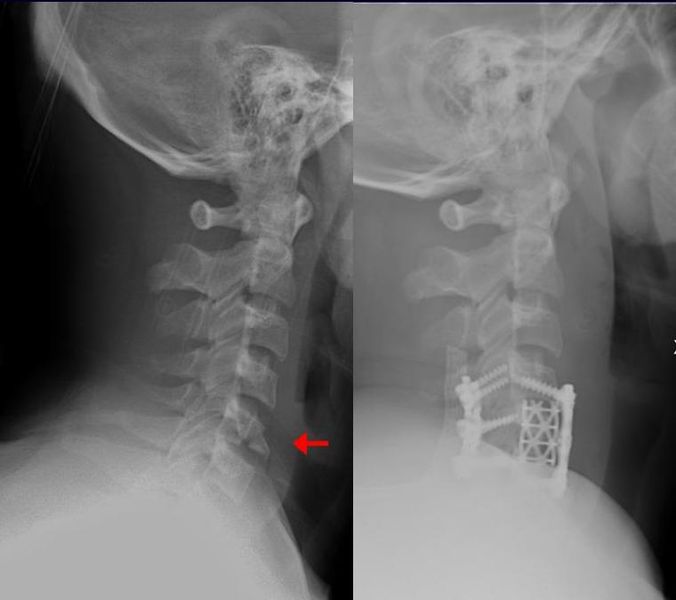

Orthopedic surgery or orthopedics, also spelled orthopaedics, is the branch of surgery concerned with conditions involving the musculoskeletal system. Orthopedic surgeons use both surgical and nonsurgical means to treat musculoskeletal trauma, spine diseases, sports injuries, degenerative diseases, infections, tumors, and congenital disorders.